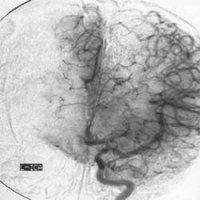

腦血管畸形1、腦動脈造影

腦動靜脈畸形有以下典型表現:①顯示畸形血管。這是特徵表現,呈一團管徑相仿相互糾纏的迂曲擴張血管。畸形血管團的範圍可小如指甲,大如手掌,多見大腦半球皮質.②異常粗大的供養動脈和引流靜脈伴局部循環加快。此為局部血流短路的表現。③血流分流現象:造影劑隨血流經畸形血管的短路大量流入靜脈,因此,血管畸形部分因血流量增加而顯影十分清楚。④血腫的表現:血管破裂出血致腦內血腫,血腫的主要表現為局部占位徵象,一股腦部動靜脈畸形無血腫時,腦血管不出現占位徵象,腦血管不移位。 2、CT表現:

5.腦血管造影:最可靠、最重要的診斷方法,動脈期可見血管團、供血動脈及早期顯現的引流靜脈。

4、腦血管造影是本病最可靠和主要的診斷方法,並能行血管內介入治療。

三術前準備

1、由於有多發的可能,術前應作全腦血管造影或雙側頸動脈造影,或按畸形血管部位推測,加作椎動脈造影。典型的腦動靜脈畸形包括供應動脈、畸形灶及引流靜脈三部分。通過造影應查清供應動脈來源及引流靜脈走向,畸形灶的部位及範圍,有無血腫等合併症,以及病人有無它處畸形。才能制訂出完善的手術計畫,也是手術成功的關鍵。